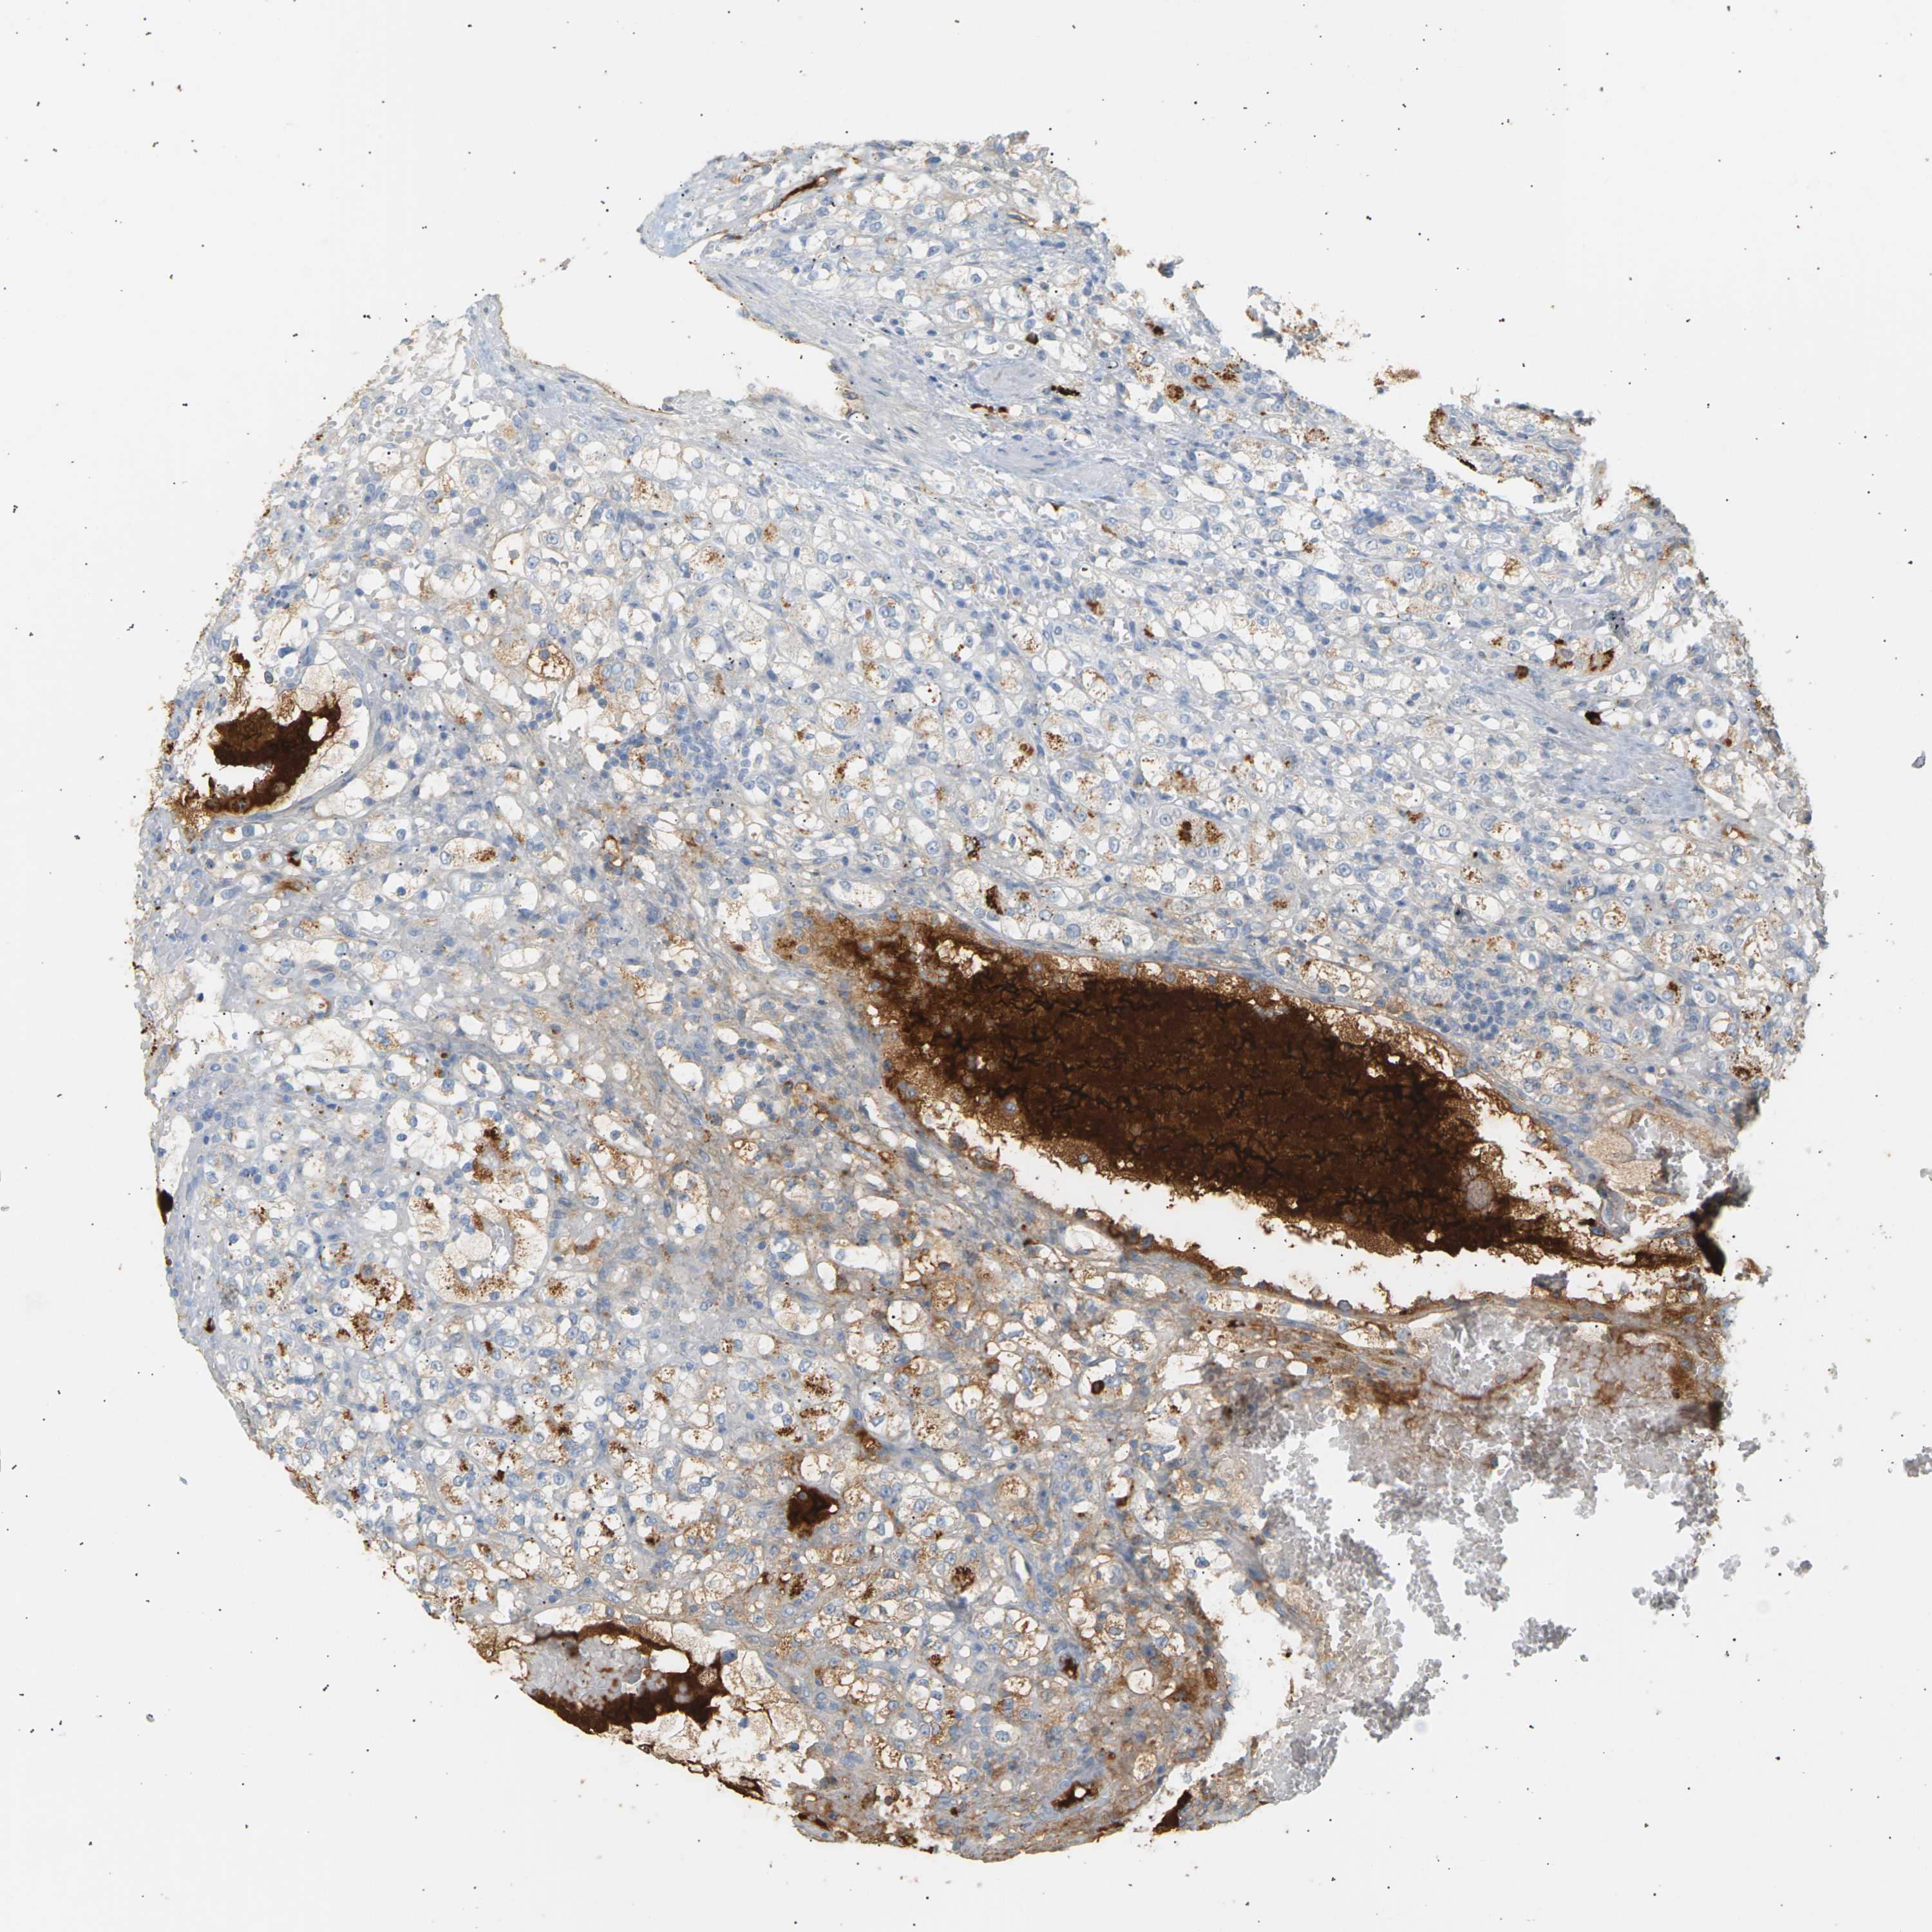

IGLC3 is not prognostic in Kidney Renal Clear Cell Carcinoma (validation)

Best expression cut offi

Based on the FPKM value of each gene, patients were classified into two groups and association between prognosis (survival) and gene expression (FPKM) was examined. The best expression cut-off refers the FPKM value that yields maximal difference with regard to survival between the two groups at the lowest log-rank P-value. Best expression cut-off was selected based on survival analysis .

When clicking on this number, the vertical dashed line indicating cut-off, the interactive survival plot, and the Kaplan-Meier curve will be adjusted to show results based on the best expression cut-off.

: 315.26

TCGA RNA samplesi

RNA-seq data is reported as average FPKM (number Fragments Per Kilobase of exon per Million reads), generated by the The Cancer Genome Atlas (TCGA) .

Normal distribution across the dataset is visualized with box plots, shown as median and 25th and 75th percentiles. Points are displayed as outliers if they are above or below 1.5 times the interquartile range. FPKM values of the individual samples are presented next to the box plot.

Average pTPM 470.8

Number of samples 100